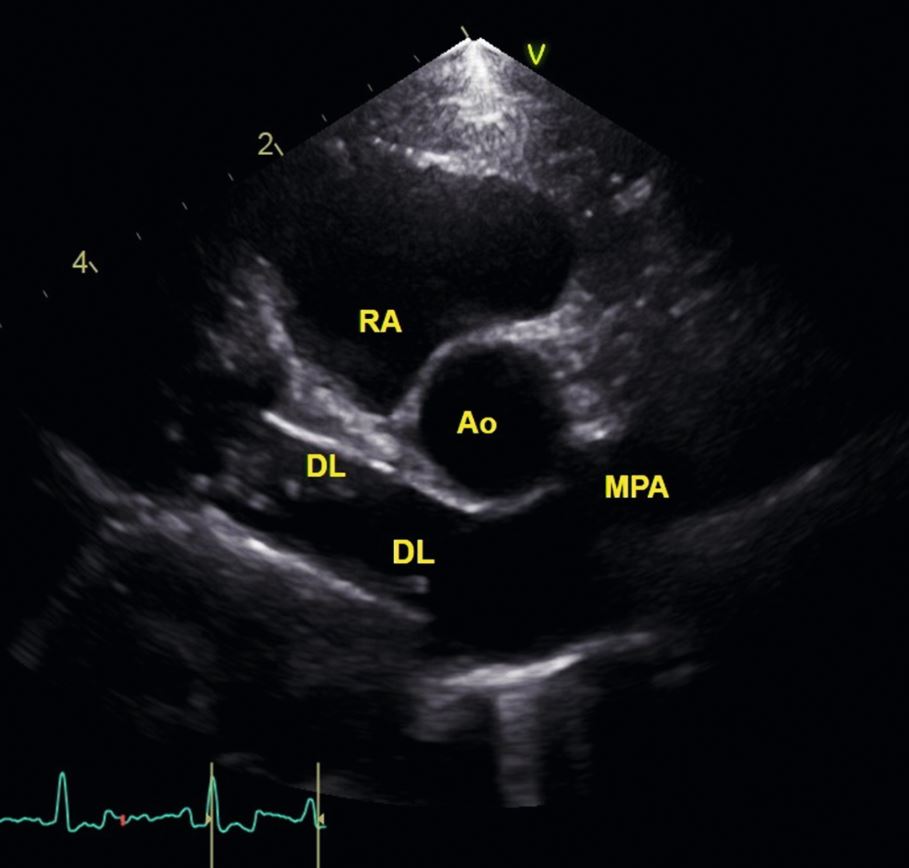

Die Bifurkation der Pulmonalarterie sollte ebenfalls sorgfältig untersucht werden, denn hier kann der erfahrene Ultraschalldiagnostiker häufig Doppellamellen (Makrofilarien) darstellen [Abb.3]. Je kleiner der Hund ist, desto wahrscheinlicher ist die Darstellung [3].

Es ist wichtig, Doppellamellen im rechten Herzen auszuschließen, da dies eine Kontraindikation für die Behandlung mit Melarsomin darstellt.